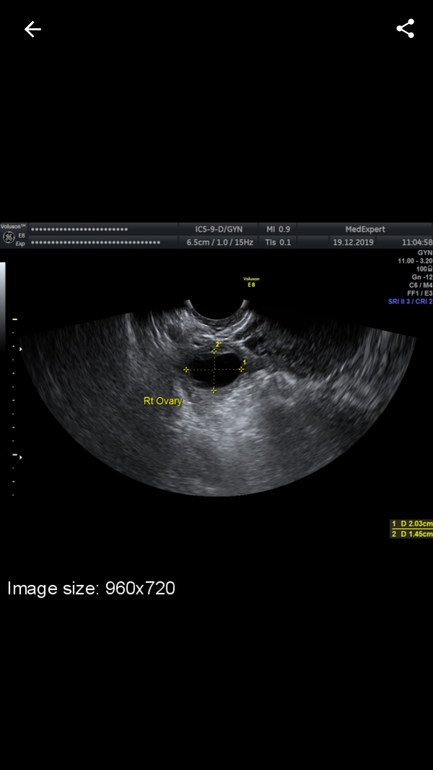

Ходила на узи ,там сказали что эндометрий 11 мм.

Желтое тело 20 мм .